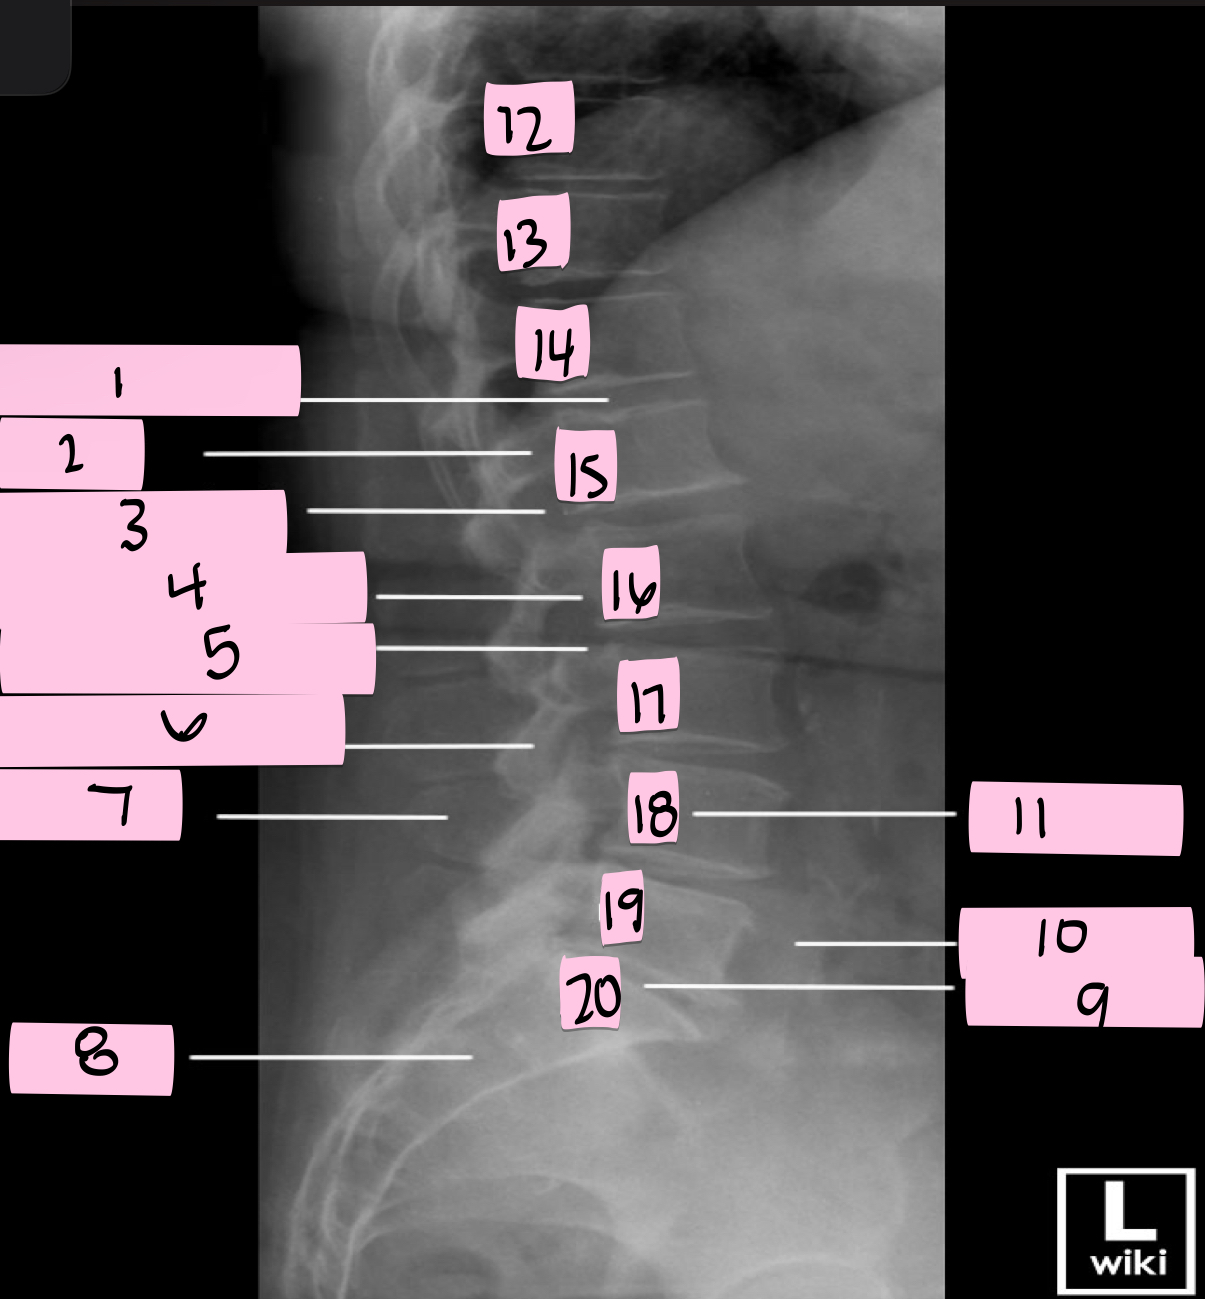

What is 1 pointing to?

Intervertebral disk

What is 2 pointing to?

Pedicle

What is 3 pointing to?

Intervertebral foramen

What is 4 pointing to?

Inferior vertebral notch

What is 5 pointing to?

Superior vertebral notch

What is 6 pointing to?

Inferior articular process

What is 7 pointing to?

Spinous process

What is 8 pointing to?

Sacrum

What is 9 pointing to?

L5 S1 joint

What is 10 pointing to?

Iliac crest

What is 11 pointing to?

Vertebral body (L4)

What is 12 pointing to?

T10

What is 13 pointing to?

T11

What is 14 pointing to?

T12

What is 15 pointing to?

L1

What is 16 pointing to?

L2

What is 17 pointing to?

L3

What is 18 pointing to?

L4

What is 19 pointing to?

L5

What is 20 pointing to?

S1